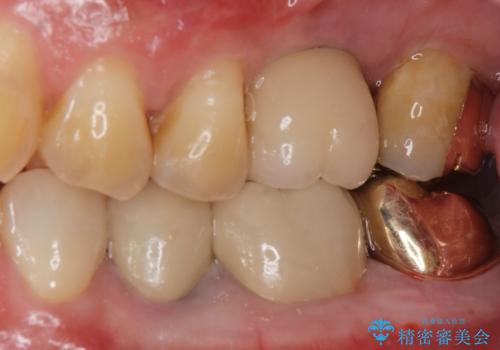

- 過去に治療したゴールドの詰め物が取れて来院。取れたのは2回目だそうです。レントゲンでは適合が良いので再装着可能だったが、

もう取れたくないとの事だったので被せ物のご案内をしました。ゴールドの被せ物の希望だったのでゴールドクラウンでの治療になりました。

適合の良いゴールドクラウンが入りました。

ゴールドは適合が良く、割れる心配もありません。

また、虫歯になるリスクも銀歯と比べて低くなります。